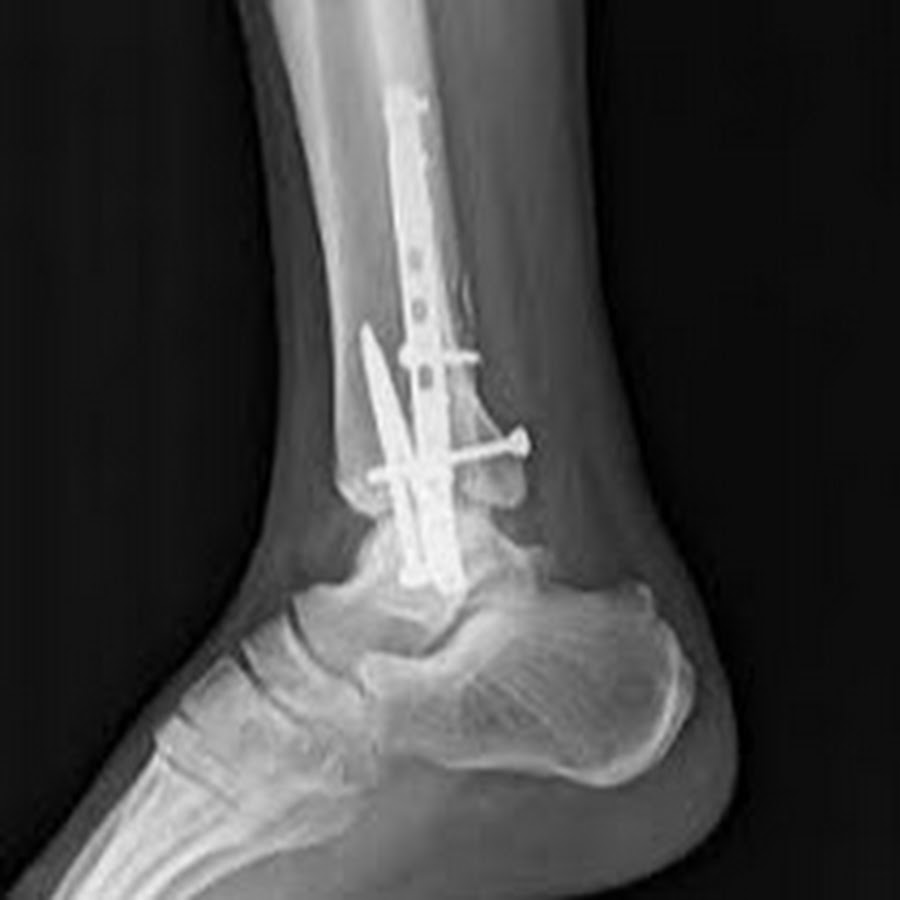

Surgical Intervention

More severe fractures may require surgical treatment:

- Open reduction and internal fixation (ORIF): Realigning bones and securing them with screws, plates, or wires

X-ray showing front view of surgical plates and screws to treat a trimalleolar fracture

X-ray showing side view of the same